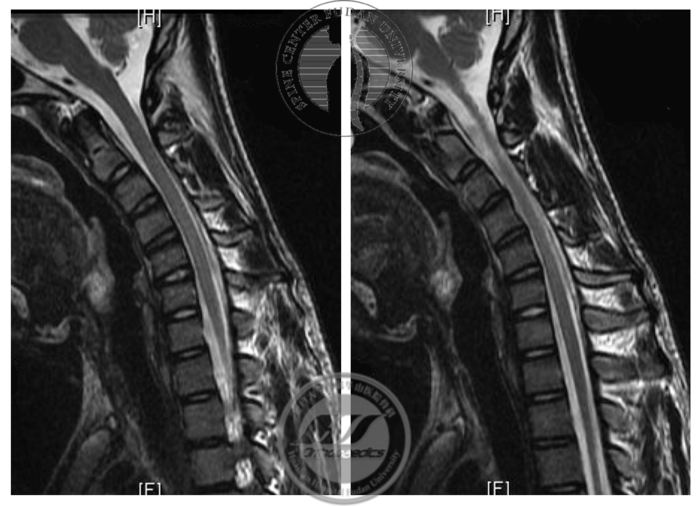

图4 屈颈位MRI T2加权像显示,硬膜囊后壁与椎管后壁分离,呈“膜-壁分离”现象;未见明显髓内信号改变

本例患者为年轻男性,起病年龄16岁,为生长发育高峰期,符合平山病流行病学特征。从初次门诊就诊的结果来看,患者有典型的单侧上肢远端肌肉萎缩、无力症状,伴有伸指震颤症状,不伴有上肢近端肌群的萎缩及下肢症状,不伴有锥体束征阳性;屈颈位MRI检查显示典型的“膜-壁分离”现象,神经电生理检查显示下颈段神经源性损害,未提示其他节段肌肉受累。至此,平山病的诊断基本确立,华山分型为Ib型。